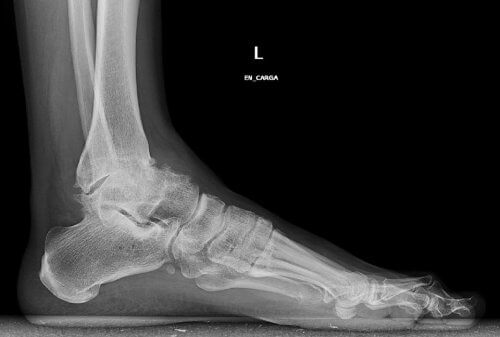

Bu tip bir artroz, ayak bileği eklemindeki kıkırdağın aşamalı olarak aşınması ve yırtılmasından kaynaklanır. Yaşlandıkça ayak bileklerinde sertleşme ve deformasyon oluşması yaygın bir durumdur.

Klasik kemik darbeleri de bu rahatsızlığa neden olabilir. Bu durumda yürümek çok acı verici olur ve hareket kabiliyeti sınırlanır.

Bu eklemde meydana gelen kıkırdak yıpranması ve yırtılmasına ilişkin ilk uyarı, yürürken hissettiğiniz acıdır. Başlangıçta uzun bir yürüyüşün ardından bu durumu fark ederiz.

- Yavaş bir şekilde ayak bileklerinde meydana gelebilecek ilerleyici deformasyon nedeniyle ağrılı topuk kemiği çıkıntısı da geliştirebilirsiniz.